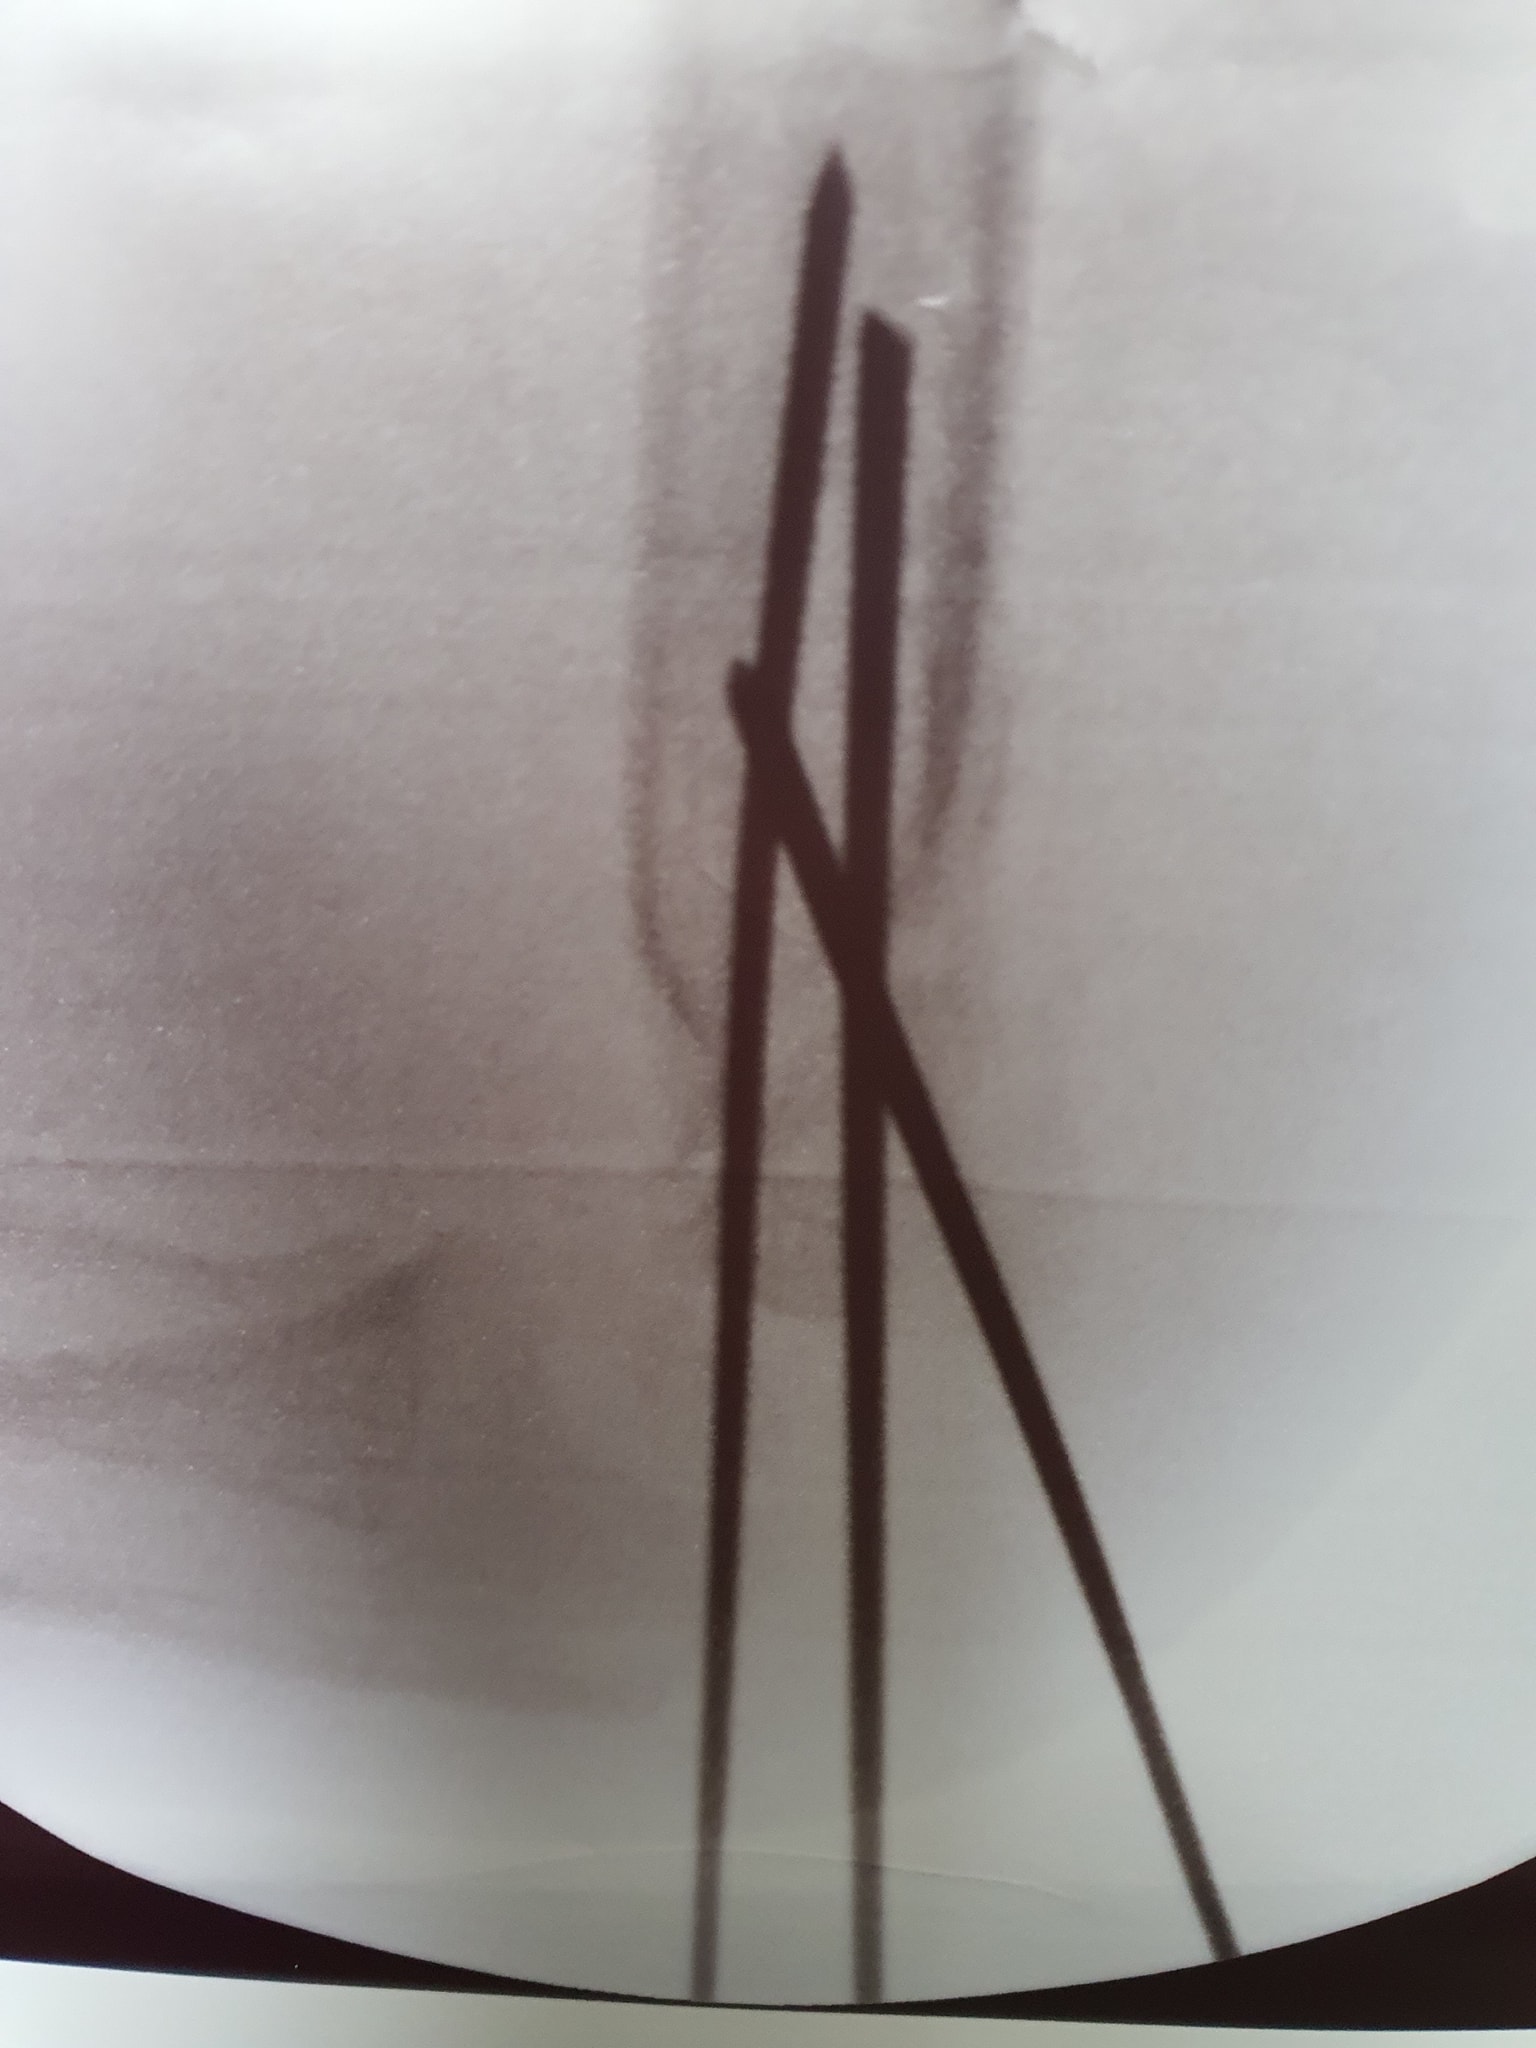

كافة انواع الكسور وعلاجها

علاج خلع الورك الولادي بكافة ا